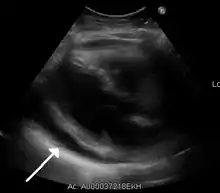

- Ultrasounds showing a pericardial effusion in someone with pericarditis

- A pericardial effusion as seen on CXR in someone with pericarditis